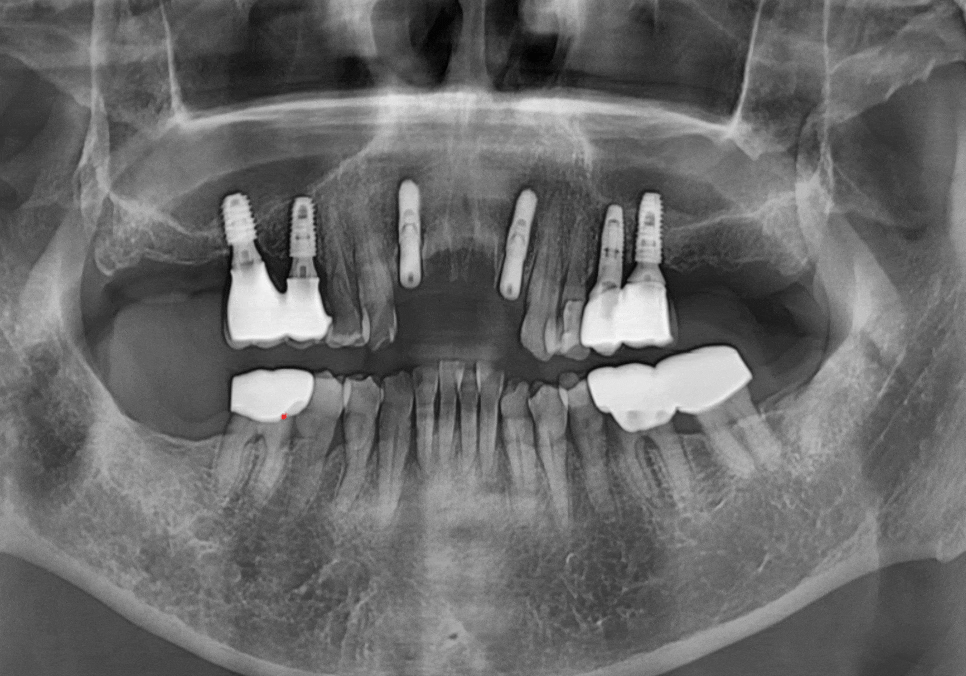

그래서 바로 치료부터 들어가기보다는,

3D CT로 안쪽 상태를

한 번 더 자세히 살펴봤습니다.

다행히

심한 염증은 없었고,

발치 후 즉시 임플란트를 진행할 수 있는

기본적인 조건은 갖추고 있었습니다.

그래서 내원 당일,

여러 각도로 살펴본 결과,

가장 안정적으로 버틸 수 있겠다는

위치를 기준으로 계획을 잡았습니다.

250221

이 기준을 바탕으로

양쪽 끝 위치에만

임플란트를 식립하고

가운데는 보철(브릿지)로 연결하는 방식으로

치료를 진행했습니다.

임플란트 뿌리가 예상했던 위치에

큰 변수 없이 잘 들어간 것을

확인할 수 있었습니다. ^^